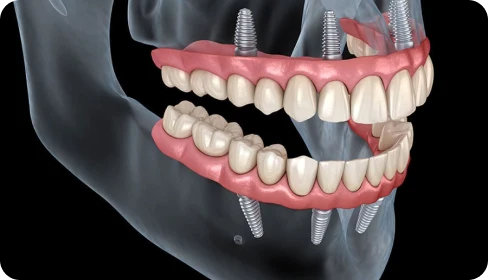

Los implantes se colocan en posiciones estratégicas y con una inclinación específica que permite evitar injertos óseos en la mayoría de los casos.

La conexión entre los cuatro implantes y la prótesis fija proporciona una gran estabilidad desde el inicio.

Con solo cuatro implantes por arcada, estratégicamente colocados, conseguimos una estructura estable sobre la que colocar una prótesis fija… el mismo día de la intervención.

Gracias a la colocación inclinada de los implantes posteriores, en muchos casos se evita la necesidad de injertos. Cada paciente se estudia de forma individual con escáner 3D para garantizar la viabilidad del tratamiento.